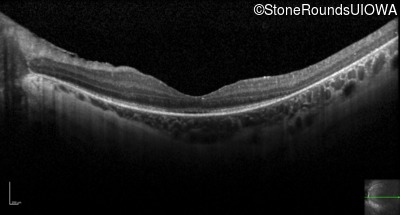

Optical Coherence Tomography - Right - 10/100 -1 sc

Exemplar / OCT Stack